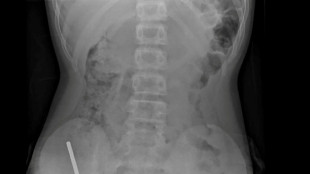

Now, the 53-year-old from Alabama has become the latest recipient of a gene-edited pig kidney -- and is currently the only living person in the world with an animal organ transplant, New York's NYU Langone hospital announced Tuesday.

Out of options, Looney applied to join a clinical trial for pig kidney transplants, and finally underwent the seven-hour surgery on November 25.

The kidney was provided by biotech company Revivicor, which breeds pigs with genetically modified kidneys less likely to be rejected by patients' immune systems.

It features 10 genetic edits to enhance compatibility with the human body -- an advance over earlier efforts that used kidneys with a single gene edit and included the pig's thymus gland to help train the host's immune system and prevent rejection.